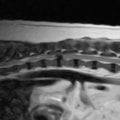

〈MRI検査:胸腰部椎間板ヘルニア2〉

突然ギャンと鳴き両後肢麻痺したとのことで来院されました。触診にて腰部の圧痛を認めました。尿失禁が認められ、深部痛覚は消失していました。聴診上での異常はみられず、後肢の股圧は触知可能でした。血液検査、胸腰椎のレントゲン検査では異常を認めませんでした。MRI検査の結果、第3腰椎領域にてT1強調画像で等信号、T2強調画像で等〜やや高信号、造影剤にて均一に増強される脊髄を腹側から圧迫する腫瘤性病変を認めました。